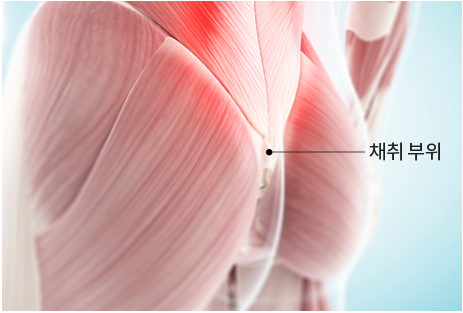

step 01. 자가진피 채취 및 봉합

엉덩이 골 사이의 안쪽을 절개하여 가장 적합한

진피를 채취하고 시간이 지나면 흉터가 눈에 띄지 않게

숨겨집니다.

엉덩이 골 안쪽으로 절개하여 속옷이나 비키니를 입어도 보이지 않습니다.

큰 불편감은 2주 내에 대부분 해소되며, 3개월 이후에는 시간이 지날수록 점차 희미해집니다.